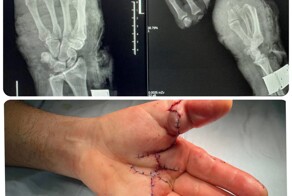

- Врачи помогли мужчине, который отрезал себе 4 пальца циркулярной пилой

- Травма на производстве. Врачи пришили сразу 5 пальцев во время одной операции